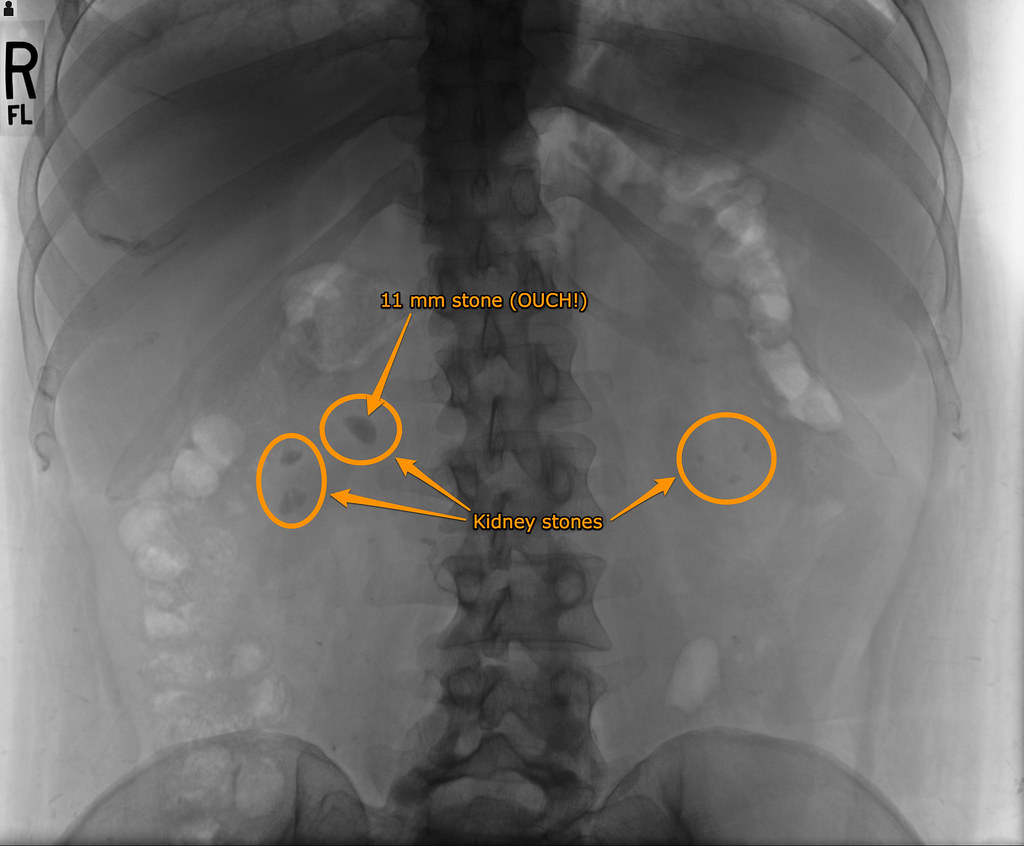

Most kidney stones are about the size of a chickpea, but they can also be as small as a grain of sand and as large as a golf ball. If a stone grows to more than 5 millimeters (0.2 in), it can cause blockage of the ureter, resulting … Stones cause symptoms like pain, trouble urinating, cloudy. But sometimes a stone will not go away. Most kidney stones pass out of the body without help from a doctor. Learn more about the different symptoms of kidney stones and how to relieve kidney stone pain at home. Pain in your back or side, blood in your urine and nausea/vomiting alongside the pain are symptoms of a kidney stone or stones. Mar 02, 2020 · below are some early signs and symptoms that may indicate a kidney stone is moving through the urinary tract.

Most kidney stones are about the size of a chickpea, but they can also be as small as a grain of sand and as large as a golf ball.